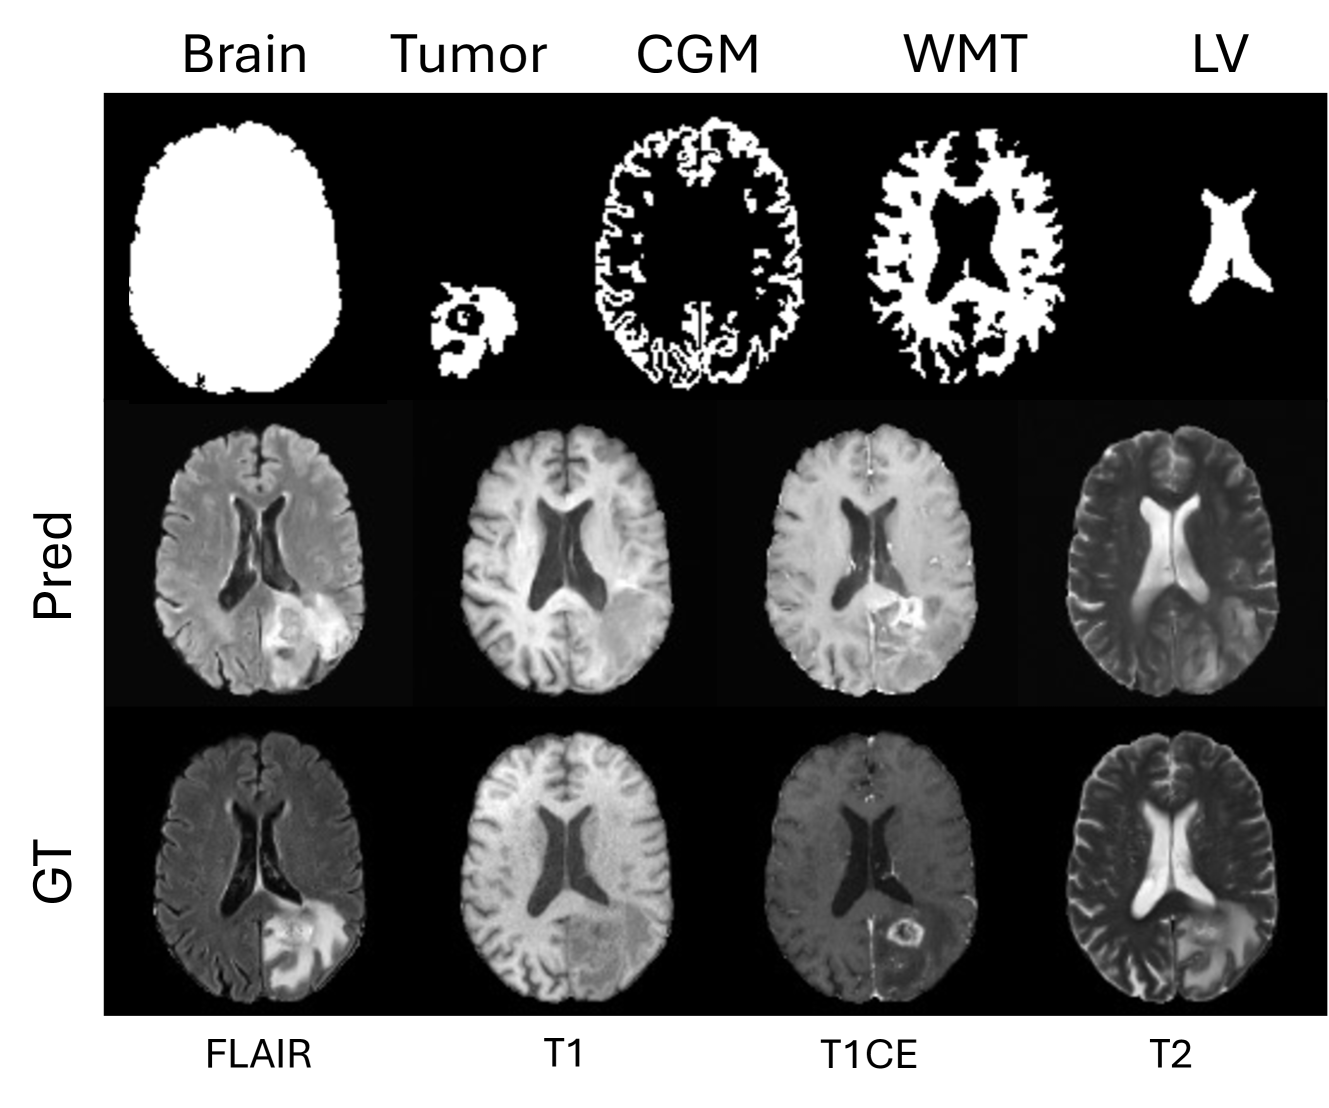

For qualitative analysis, we compared the images generated by BrainMRDiff with those produced by different baseline models. In Fig. 6, we show a comparison of generated images from DDPM, ControlNet trained with BM, ControlNet trained with tumor segmentations, and BrainMRDiff, alondside the corresponding real FLAIR sequence from the BraTS-AG dataset. Neuroradiologist’s (8 years exp) interpretation: We observe that since DDPM lacks anatomical controls, it generates visually plausible MRI sequences but fails to preserve anatomical structures. In contrast, ControlNet introduces anatomical awareness, but its performance remains suboptimal in accurately capturing both brain and tumor morphology. BrainMRDiff, however, achieves superior fidelity by preserving both brain anatomical details and tumor topology, resulting in highly realistic and anatomically coherent MRI sequences. In Fig. 7, we further illustrate real and BrainMRDiff-generated images along with the corresponding anatomical masks for two cases from the BraTS-AG dataset, showcasing our methods ability to generate high-quality and anatomically-accurate images. More examples are provided in the Supp. (Figs 9 and 11).

Brain anatomy. In addition to the tumor, we use several other anatomically important structures namely White Matter Tracts (WMT), Cortical gray Matter (CGM), Lateral Ventricles (LV), and Brain Masks (BM). The detailed explanation about the generation of the structures are discussed in Sec. 4.1. In Fig. 3, we show examples of the different structures. More examples are shown in Supplementary (Figure 10).